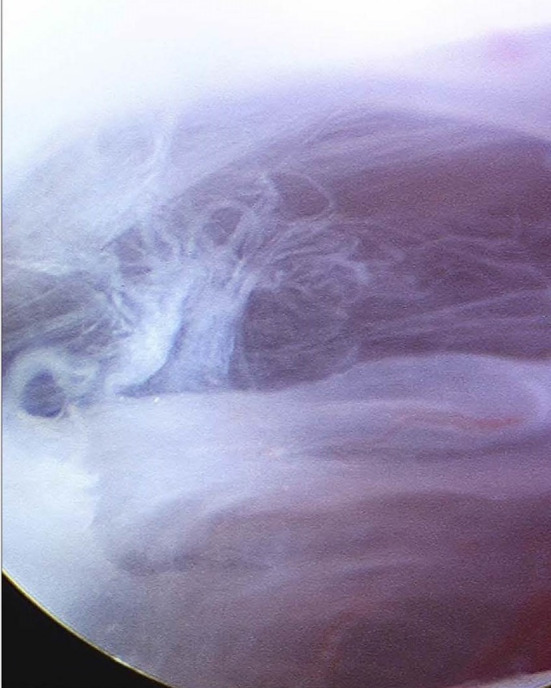

The first sharp cannula and trochar are inserted at point A. An initial small 3-mm skin incision is made, and the trochar inserted at an upwards, forward and medial trajectory. A 19-gauge needle is inserted alongside the cannula for irrigation. The sharp trochar is withdrawn, and the 2.7 mm 30° rod lens video arthroscope placed into the cannula. A detailed examination of the superior joint space is now performed (Fig. 9).

Fig. 9.

Arthroscopic view of the superior joint space

This examination gives an initial impression of the extent of the intra-articular pathology of the superior joint space involving the eminence, glenoid fossa and the intra-articular disc.